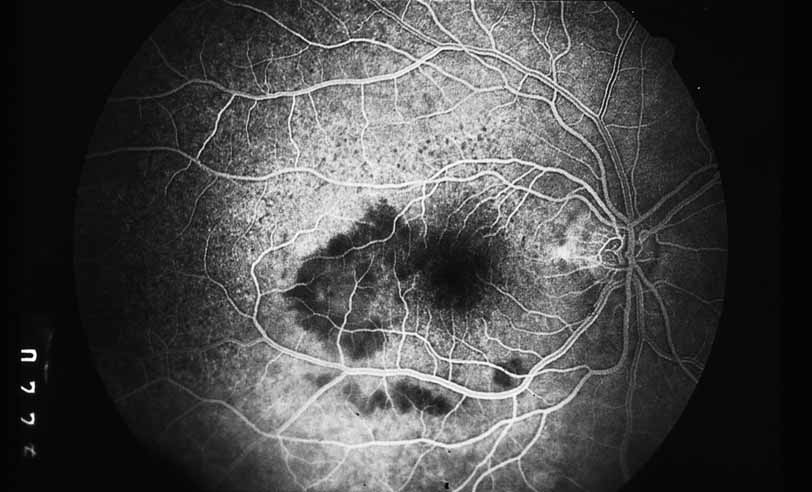

Fig. 3 Luetic neuroretinitis. Early-frame angiogram of eye of middle-aged man who presented with vision loss and a peculiar yellow---green discoloration of the outer retina and pigment epithelium. The patient was not known to be immunosuppressed, and subsequent serologic testing confirmed the presence of a positive VDRL and FTA-ABS. The early frame of the angiogram demonstrates a broad area of hypofluorescence corresponding to the clinical lesion. Note the subtle punctate leopard spots above the lesion.

As an example, patients with posterior segment involvement by the spirochete Treponema pallidum may manifest visual loss on the basis of a large number of different mechanisms.16–21 These include perioptic neuritis, retinal periphlebitis or periarteritis, diffuse neuroretinitis, cystoid macular edema, or choroidal neovascularization. Fluorescein angiography may be helpful not only in establishing the causative agent but also in determining the predominant mechanism of visual loss (see Figs. 4 and 5).